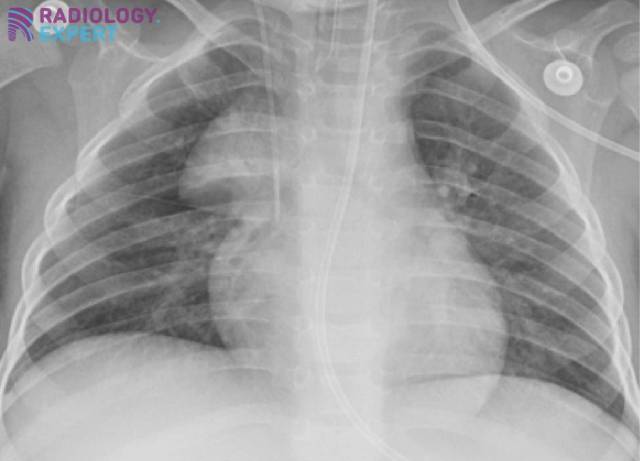

Vormvariant vnormale thymus; sail sign. Vormvariant vnormale thymus; sail sign.